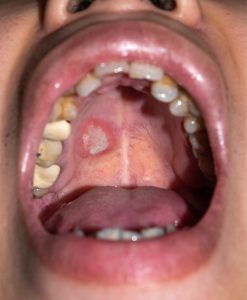

- Non-Healing Sores: Mouth ulcers or lesions that persist beyond normal healing timeframes may indicate developing malignancy requiring immediate professional assessment.

- Color Changes: White patches (leukoplakia), red patches (erythroplakia), or mixed red-and-white lesions represent potentially pre-malignant conditions needing expert evaluation.

- Texture Abnormalities: Rough, crusty, or eroded areas in the mouth that feel different from normal tissue may signal early cancer development.

Squamous cell carcinomas develop in the flat cells lining the mouth and throat, representing the vast majority of oral cancer cases. These cancers most commonly affect the tongue, floor of the mouth, and lip borders, often beginning as small, painless lesions that gradually enlarge and may ulcerate if left untreated.